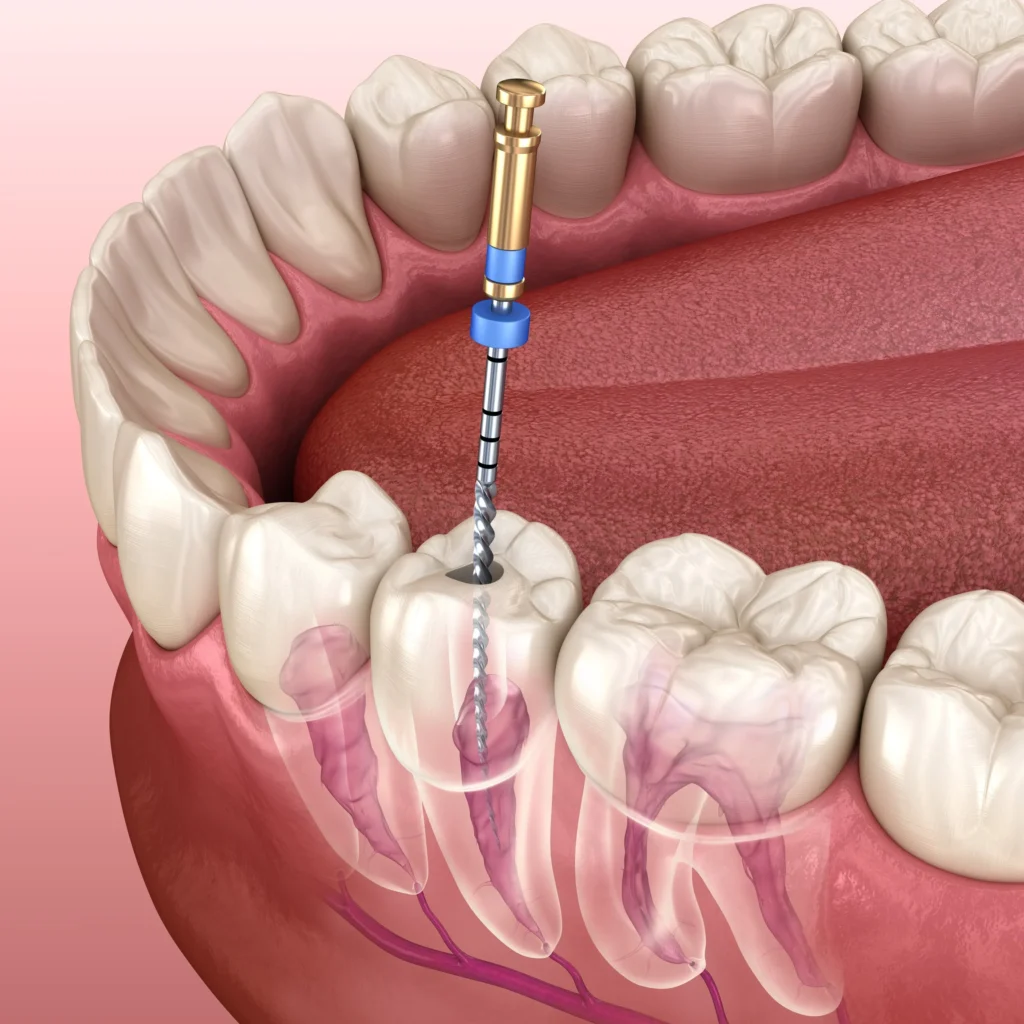

Root canal treatment is one of the most effective procedures to save a severely decayed or infected tooth. At Pathak Dental Clinic, we provide painless root canal treatment in Bhubaneswar using advanced rotary instruments and modern anesthesia techniques.

During the procedure, the infected pulp inside the tooth is carefully removed, the canals are cleaned and disinfected, and the tooth is sealed to prevent future infection. Our approach ensures minimal discomfort and faster recovery.